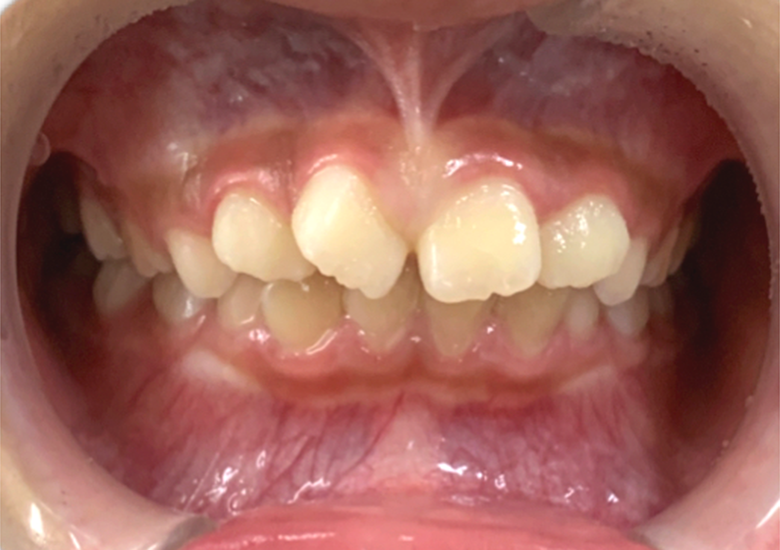

治療前

前歯のガタガタが気になる |

叢生/アクティビティ+インビザライン矯正 |